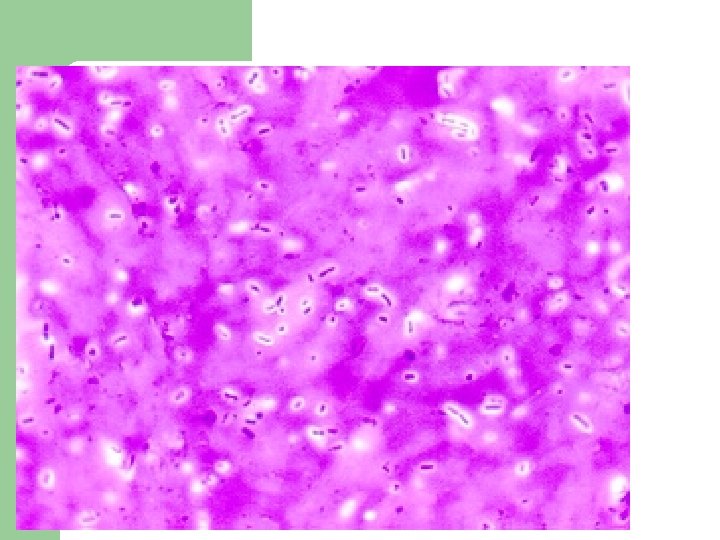

Mycobacterium tuberculosis